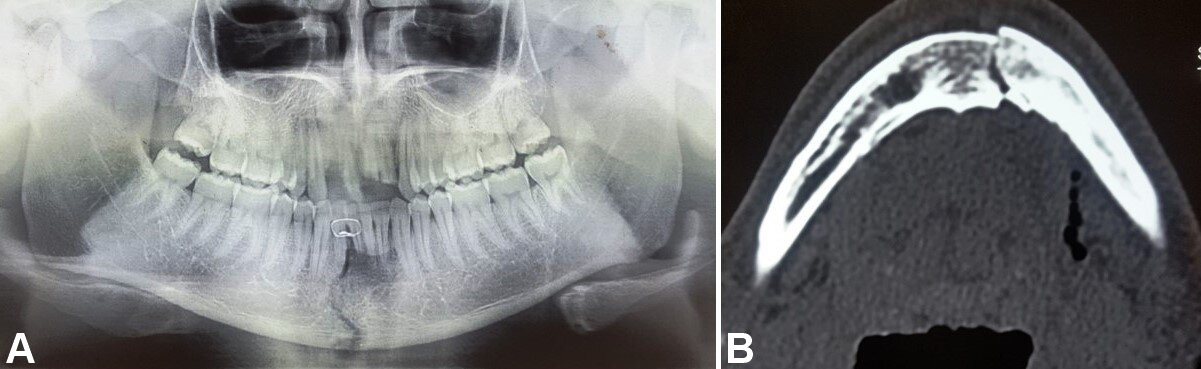

Patients with comminuted mandibular fractures, concomitant midface and dentoalveolar fractures, infected fractures, partial or complete edentulism, and systemic diseases were excluded from the study. Detailed preoperative medical and clinical examinations were conducted. The diagnosis of undisplaced or minimally displaced symphyseal or parasymphyseal fractures was based on clinical and radiographic assessments. Orthopantomograms were used to evaluate mandibular lower border displacement, with displacements of less than 5 mm included in the study (Figure 1). Advanced diagnostic techniques, including low-dose radiation and 3D assessments using computed tomography (CT), cone beam computed tomography and magnetic resonance imaging, facilitate comprehensive evaluation of head and neck disorders, including the assessment of both soft and hard tissue injuries.5, 6, 7 Therefore, CT with 3D reconstruction of the face was performed, with fractures exhibiting bucco-lingual overlap of less than 5 mm included in the study (Figure 1).

In group A, fixation was performed using 2 titanium microplates (0.8-mm, 4-hole design with a gap) and 8 microscrews (1.5 mm × 8 mm and 1.5 mm × 10 mm), which were placed subapically and at the inferior border of the mandible according to Champy’s lines of osteosynthesis (Figure 2, Figure 3, Figure 4).